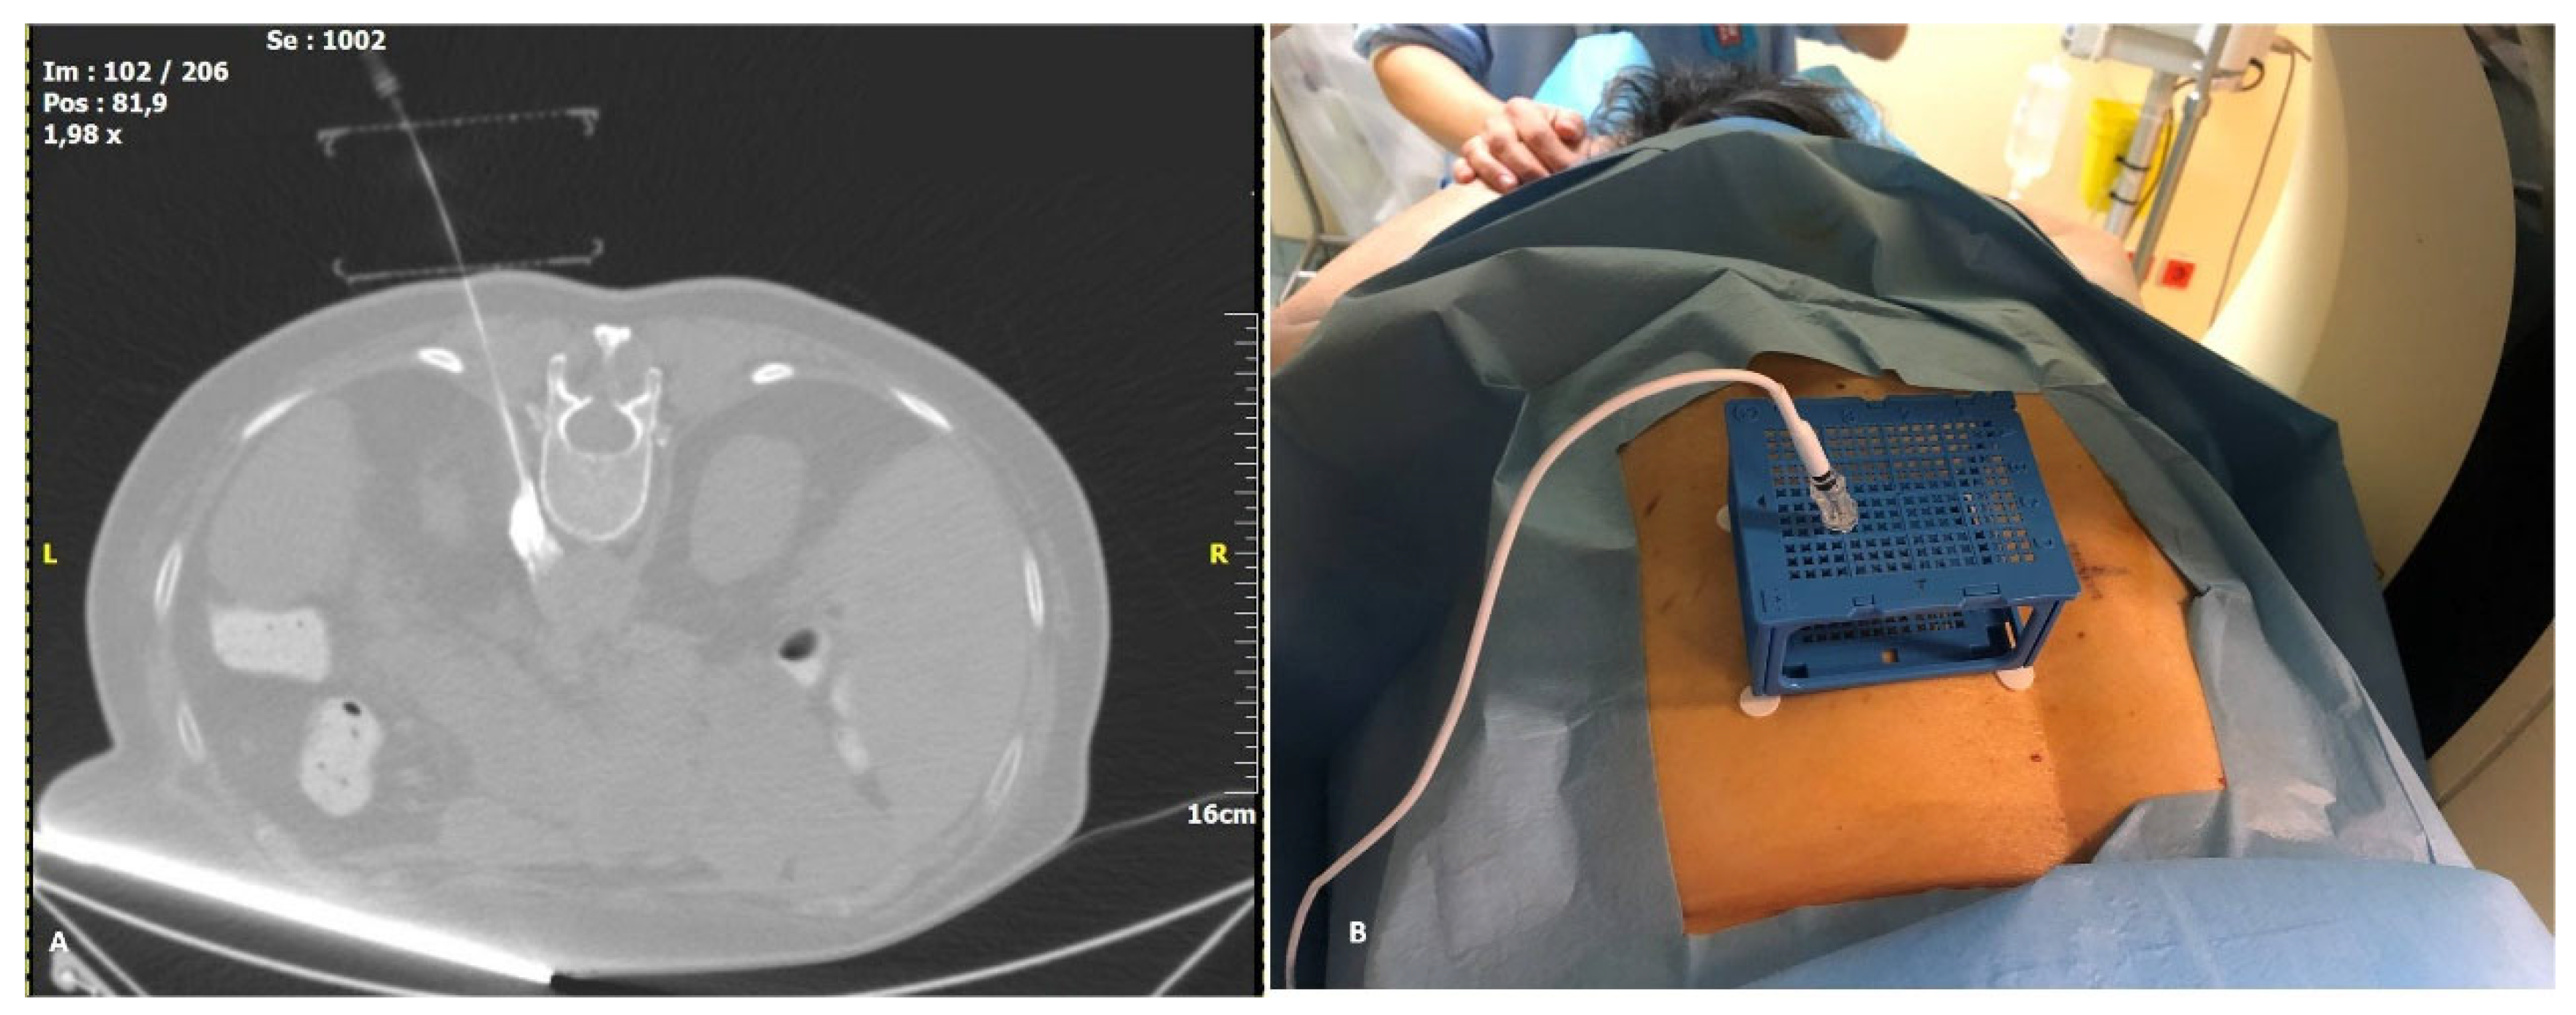

Figure 4. Final image prior to treatment: (A): Corrected (MPR) CT image of the cube with the needle in place, showing the whole needle trajectory. At the tip of the needle, there is hyperdense contrast pooling, verifying the correct needle position. (B): Actual image of the needle and electrode in place inside the cube.

Patients were placed in prone position on the CT table. Prior to radio frequency ablation all patients were sedated with incrementally increasing i.v doses of fentanyl and propofol. Vital signs were monitored throughout the procedure, including oxygen saturations and ECG. Computed tomography sequential scans (120 Kv, 240 mAs wavelength and 2 mm slice thickness) were performed for planning, targeting and intra-procedural modification. Based on a lateral and an antero-posterior topogram at the 12th thoracic vertebral body (TH12), the approximate puncture site was marked on the skin. After skin disinfection, the PC was placed over the approximate puncture site and a CT planning scan was obtained during breath hold of the patient. The images were transferred to the software as described above and the access route to the target, antero-lateral on the TH12 vertebral body, was determined. The coordinates to introduce the needle were recorded for the upper and lower plate (Figure 3B). A 15 cm long, 20–gauge radiofrequency needle with a 10 mm active tip (Diros OWL® RF Probe, Diros Technology Inc., Ontario, ON, Canada) was inserted and its approach until the level of splanchnic nerve plexus antero-lateral to the vertebral body was evaluated with sequential CT scans until the designated target was reached. The cube was collapsed, as designed, after the needle was firmly introduced a few centimeters into the patient. The neurolysis session was performed with an ablation protocol according to the manufacturer’s guidelines (two circles of 90 s at a temperature between 80–90 °C) (Figure 4A). Patients remained in the hospital overnight before discharge. All five procedures were performed by two highly experienced interventional radiologists who had no prior experience with the CNS.

In contrast with other systems, the CNS offers stability of the needle during image acquisition (Figure 4B) as well as guidance. This could be of interest especially in superficial lesions as it is held in place by the cube holes. Repositioning of the needle and/or correction of the angulation can be performed when the upper surface collapses over the lower one after needle insertion. In summary, given the ease of installation and use of the CNS, as well as the high degree of accuracy attainable with the system, we consider the CNS an advantageous addition to routine clinical practice. Improvements such as larger through holes and removable plates after needle insertion provide CNS with the potential to be widely applied for a variety of clinical indications.